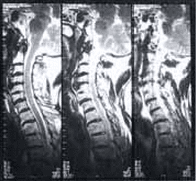

Figura 1. Radiografía de Columna Cervical, proyección lateral: Pérdida de la cifosis normal. Osteopenia generalizada. Calcificación del ligamento longitudinal anterior a lo largo de toda la columna. Pérdida de la definición de las articulaciones interfacetarias. Puente óseo posterior entre C6 y C7.

Figura 2. Resonancia Magnética de columna cervical T1: Se demuestra engrosamiento del ligamento longitudinal anterior con señal hipointensa, lográndose diferenciar fácilmente del cuerpo vertebral. Puente óseo posterior entre C5_C6. Aumento de intensidad de la señal de los discos intervertebrales.